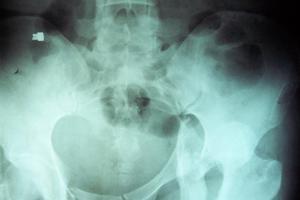

应与腓总神经损伤相鉴别。坐骨神经损伤为腰髓4、5和骶髓1、2、3神经根组成。多由股部或臀部火器伤引起,有时髋关节脱臼和骨盆骨折亦可合并坐骨神经损伤。髋关节后脱位、臀部刀伤、臀肌肉挛缩手术伤以及臀部肌注药物均可致其高位损伤,引起股后部肌肉及小腿和足部所有肌肉全部瘫痪,导致膝关节不能屈、踝关节与足趾运动功能完全丧失,呈足下垂。小腿后外侧和足部感觉丧失,足部出现神经营养性改变。由于股四头肌腱全,膝关节呈伸直状态,行走时呈跨越步态。如在股后中、下部损伤,则蝈绳肌正常,膝关节屈曲功能保存。可以此进行鉴别。